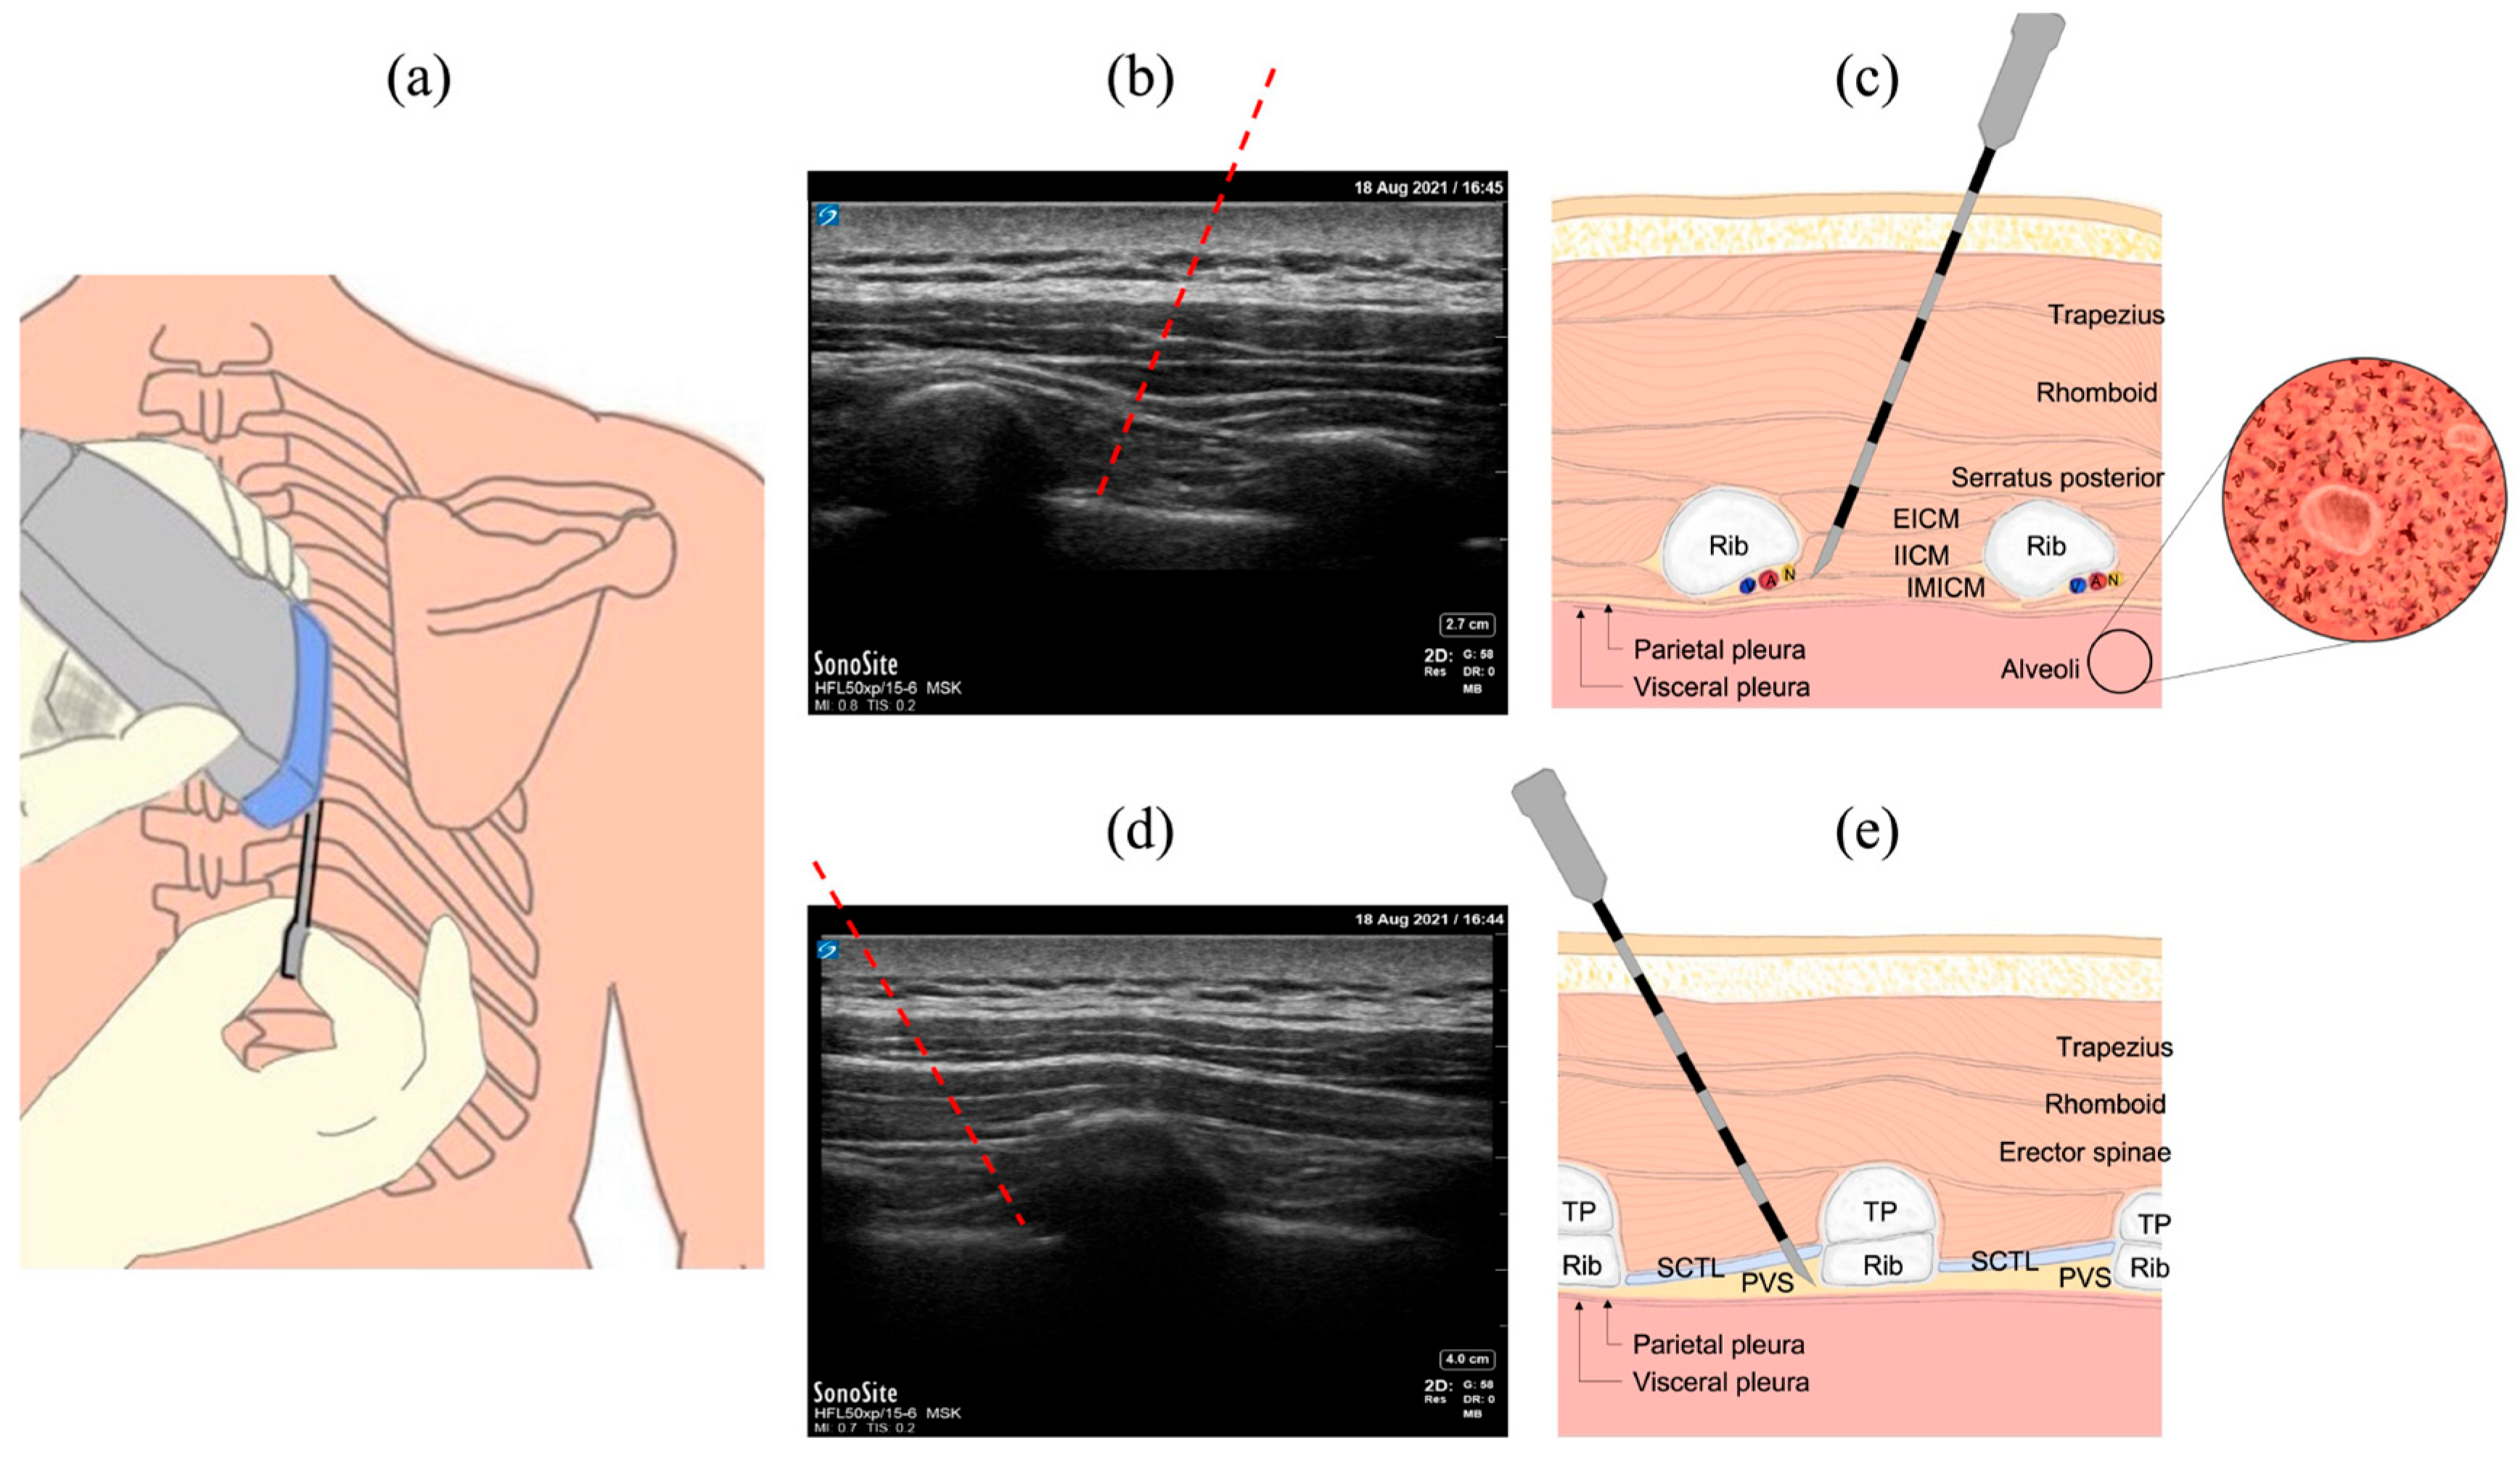

2.1. Common Procedures in the Thoracic Region

2.2. The INUS System